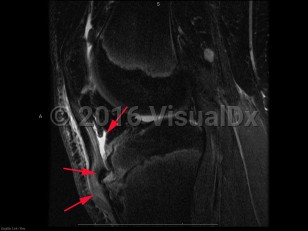

Osgood-Schlatter disease in Adult

Causes / typical injury mechanism: Osgood-Schlatter disease (OS), also known as juvenile osteochondrosis of the tibial tubercle, is a disorder involving inflammation, pain, and swelling of the tibial tuberosity. It is most common in young adolescents, particularly those regularly involved in athletics. OS typically occurs soon after a growth spurt. Symptoms last for 12-18 months, often resolving spontaneously with the closure of the physeal plate of the tibia, although there is a small subset of patients who experience pain after skeletal maturation.

Pathophysiology: The underlying pathophysiology of OS is poorly understood. Its association with sports participation has led to the hypothesis that it is related to repeated small injuries to the developing knee associated with traction from the patellar tendon.